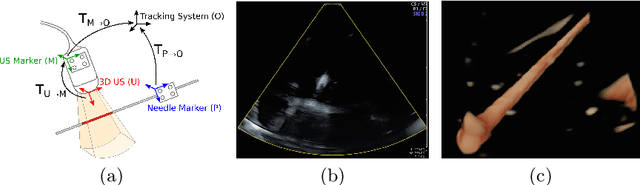

We propose a minimal solution for the similarity registration (rigid pose and scale) between two sets of 3D lines, and also between a set of co-planar points and a set of 3D lines. The first problem is solved up to 8 discrete solutions with a minimum of 2 line-line correspondences, while the second is solved up to 4 discrete solutions using 4 point-line correspondences. We use these algorithms to perform the extrinsic calibration between a pose tracking sensor and a 2D/3D ultrasound (US) curvilinear probe using a tracked needle as calibration target. The needle is tracked as a 3D line, and is scanned by the ultrasound as either a 3D line (3D US) or as a 2D point (2D US). Since the scale factor that converts US scan units to metric coordinates is unknown, the calibration is formulated as a similarity registration problem. We present results with both synthetic and real data and show that the minimum solutions outperform the correspondent non-minimal linear formulations.